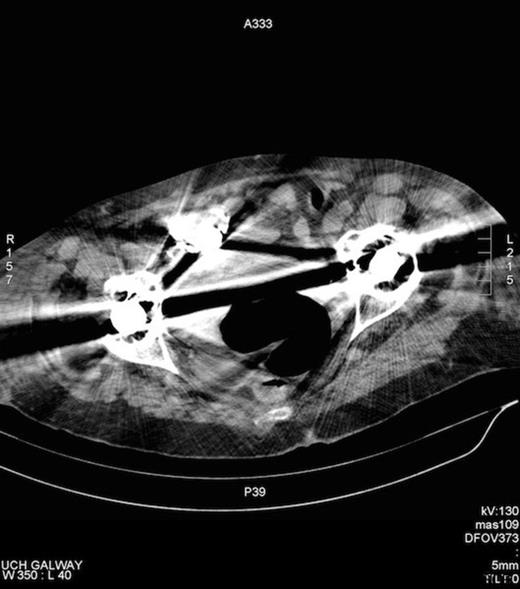

Amyand’s hernia is difficult to diagnose clinically and is rarely diagnosed preoperatively. In a review of 60 cases over a 12 year period only one case was diagnosed pre operatively (7). The difficulty in diagnosis has its origins in the considerable variation of symptoms that patients present with, depending on if the appendix is normal, incarcerated or perforated with the commonest presenting symptom being painful inguinal or inguinoscrotal swelling while the history and examination usually point to an incarcerated hernia (8). Fever and leukocytosis are inconsistent findings. Preoperative CT has revealed the previously unsuspected diagnosis in an occasional report and is useful in establishing the diagnosis early but is not routinely used in clinical situations where a complicated hernia is suspected. Laermann et al illustrated that combining CT with Multi Planar Reconstruction is the most useful technique, to better visualise the appendix and its relationship with surrounding structures, thus aiding in confidently making the correct diagnosis pre-operatively (6). In our case, the appendix could not be visualised, given that the patient has bilateral hip prosthesis, which produced artefact at the level of the appendix. (Figure 4.)

Artefact on CT, secondary to bilateral hip prosthesis, which obscures the appendix.